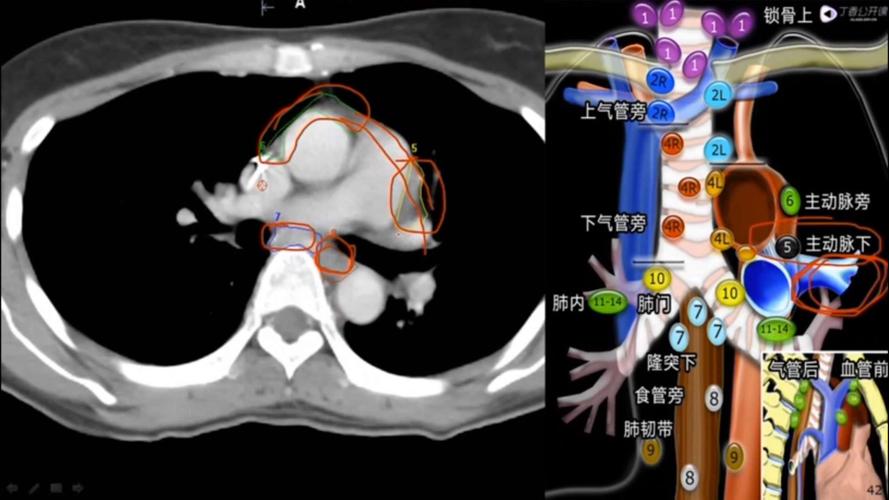

纵隔淋巴结新分区ct

肺癌纵隔淋巴结分区

今日分享 — 纵隔淋巴结分区图谱

纵隔淋巴结分区的快速记忆

纵隔淋巴结分区图谱(美国胸科协会) 发表者:陈海石 (访问人次

纵隔淋巴结分区图谱